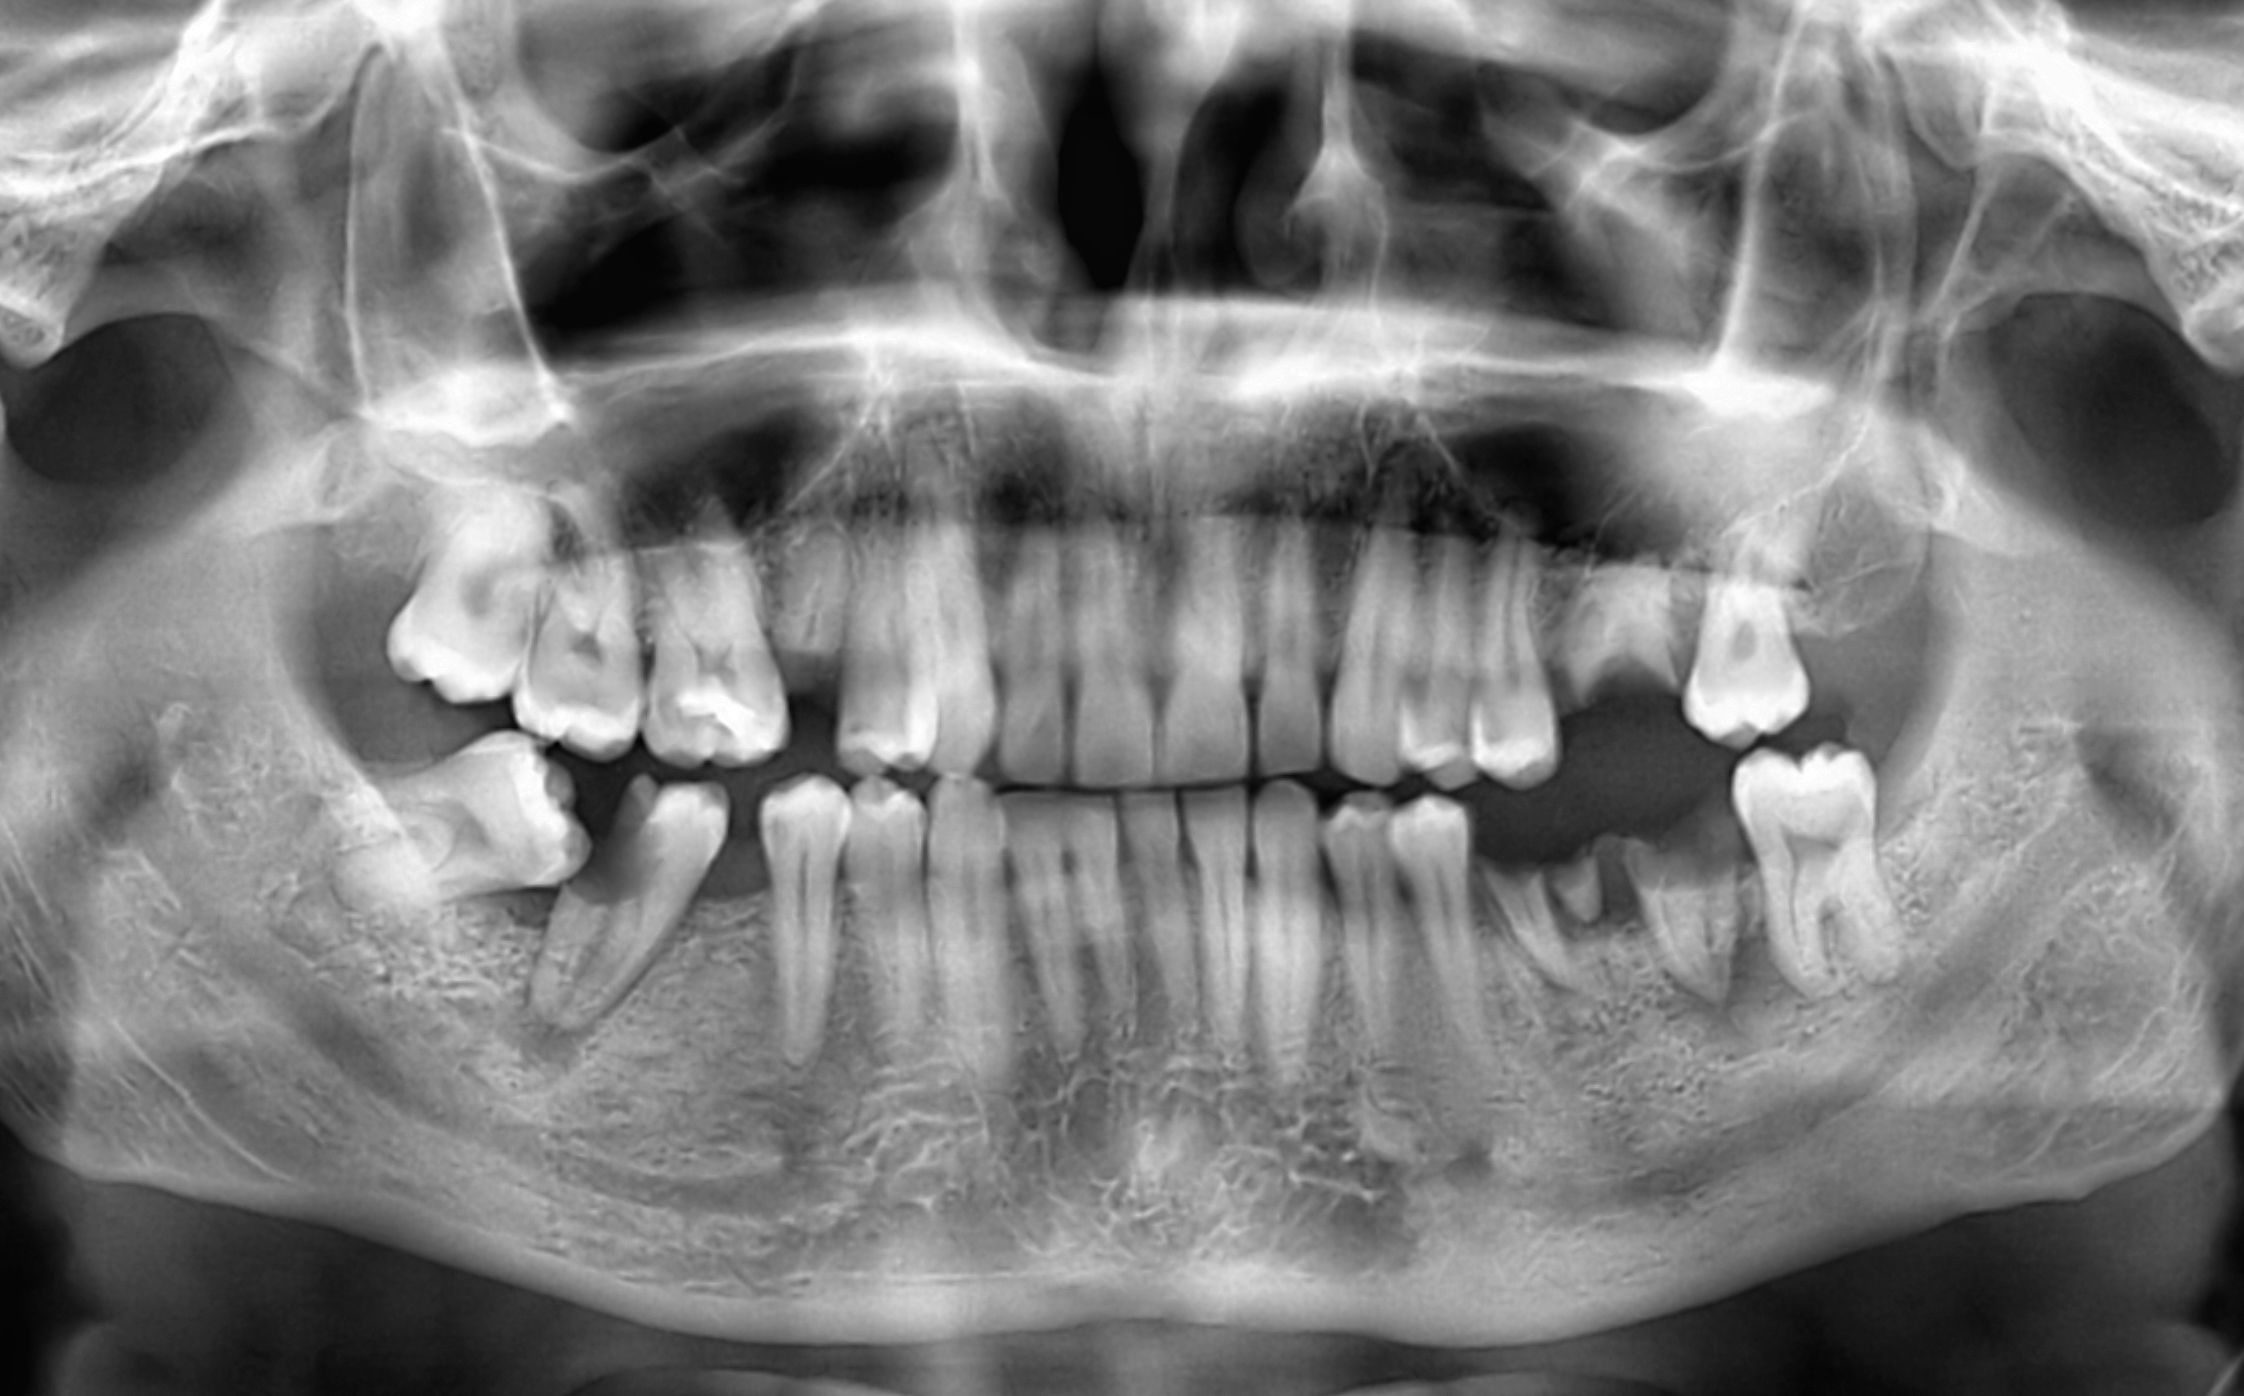

Before extraction, Dr. Stein will take x-rays to examine your tooth and determine the simplest way to remove it. Then he will administer local anesthesia, as well as a more powerful sedative if desired. During a simple extraction, Dr. Stein will loosen the tooth with a gentle back and forth motion and then carefully lift it from the socket.

If you have an impacted tooth, or if your tooth has broken off near the gumline, Dr. Stein will perform a surgical extraction. During this type of procedure, he will create an incision in the gums through which he can access the tooth. Even these more complicated procedures usually involve minimal discomfort and take an hour or less.